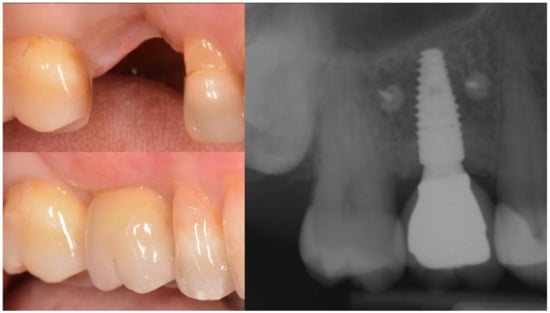

Three months after implant surgery the fixture was restored with a ceramic crown and a radiograph taken 5 years after augmentation. Figure 4 not only shows the perfect maintenance of the osseointegration after loading, but also how the GTR effect is visible on the mesial of tooth 26 with an attachment gain of 6 mm; the probing (PPD) at the time of recall was 3 mm The tooth remained in function and the patient can clean the area well with interproximal tooth brushes and dental floss.

Figure 4.

Rx taken at a 5 year follow-up showing the stability of the regeneration on both implant and tooth side.